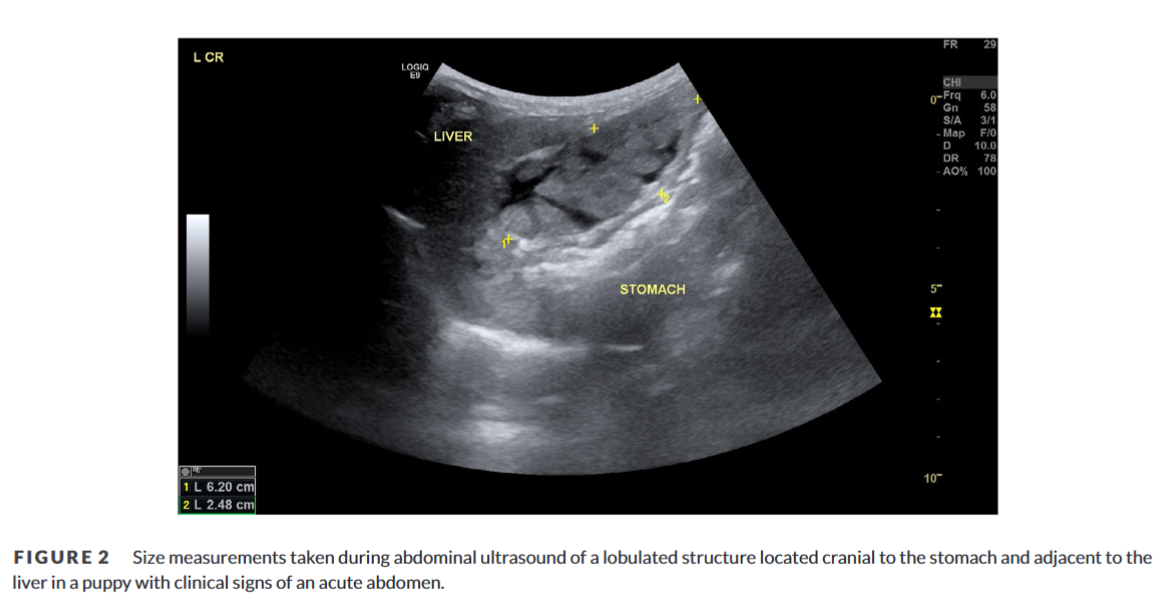

이번에는 췌장영전 케이스가 보고되어 소개한다.